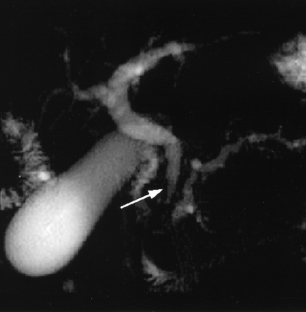

Cholestasis may result from hepatocellular (intrahepatic) disease or biliary tract (extrahepatic) abnormalities. Etiologies causing extrahepatic cholestasis are extremely diverse and invasive procedures, such as endoscopic retrograde cholangiopancreatography (ERCP) and percutaneous transhepatic cholangiography (PTC), were previously required to establish the diagnosis. Due to refinements of magnetic resonance imaging (MRI) techniques, the patient with extrahepatic cholestasis currently can be evaluated noninvasively, and the information revealed frequently exceeds the findings obtained by ERCP and PTC. In this essay, we illustrate the classic MR cholangiographic (MRC) and MRI features of a variety of disorders causing extrahepatic cholestasis, including non-neoplastic disorders of the biliary tract (congenital abnormalities, infectious processes, iatrogenic disorders, and postsurgical complications) and neoplastic conditions (e.g., tumors of the pancreas, biliary tree, liver, ampulla, and regional lymph nodes). In most cases, familiarity with the key MRC features in addition to information obtained via cross-sectional MR images provide sufficient information for adequate lesion characterization.